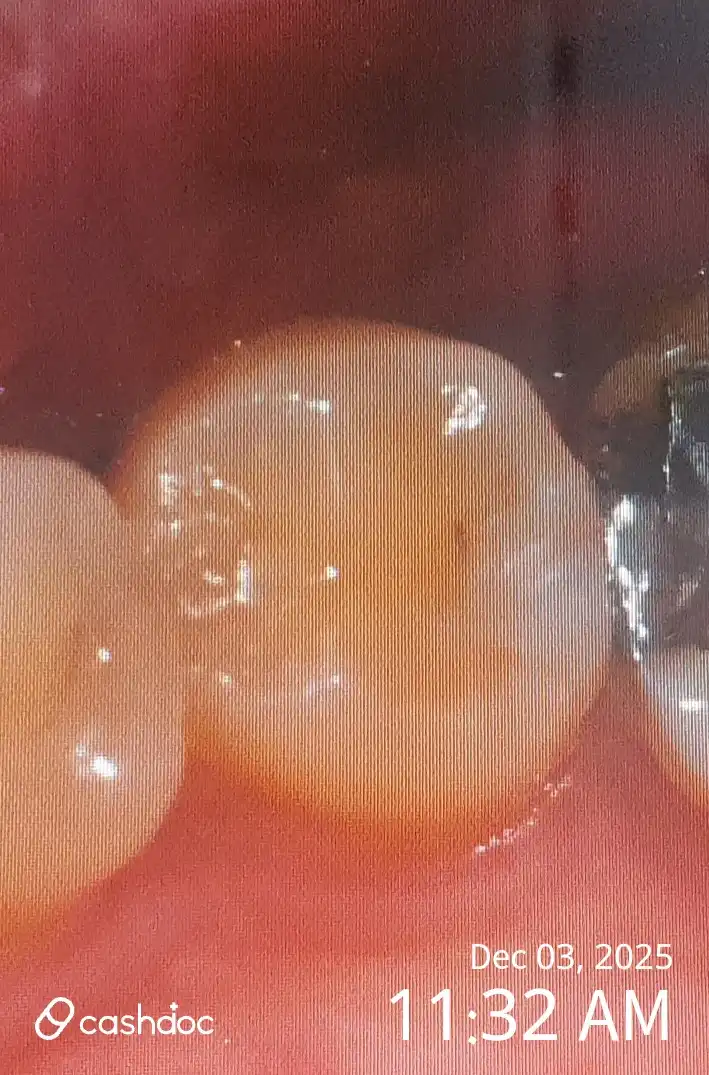

치아가 깨져서 방문하여 크라운 치료를 받았습니다 이준식 의사님 친절하시고 치료도 잘해주시는 것 같아요 질문하는것도 잘 답변해주시고 좋았습니다 통증은 거의 없었고, 치아마다 차이가 있었지만 대략 10일정도 후엔 차가운 물을 마셔도 시린증상까지도 없어졌네요 사진은 비포뿐이네요..

김한*25.12.031번째 방문